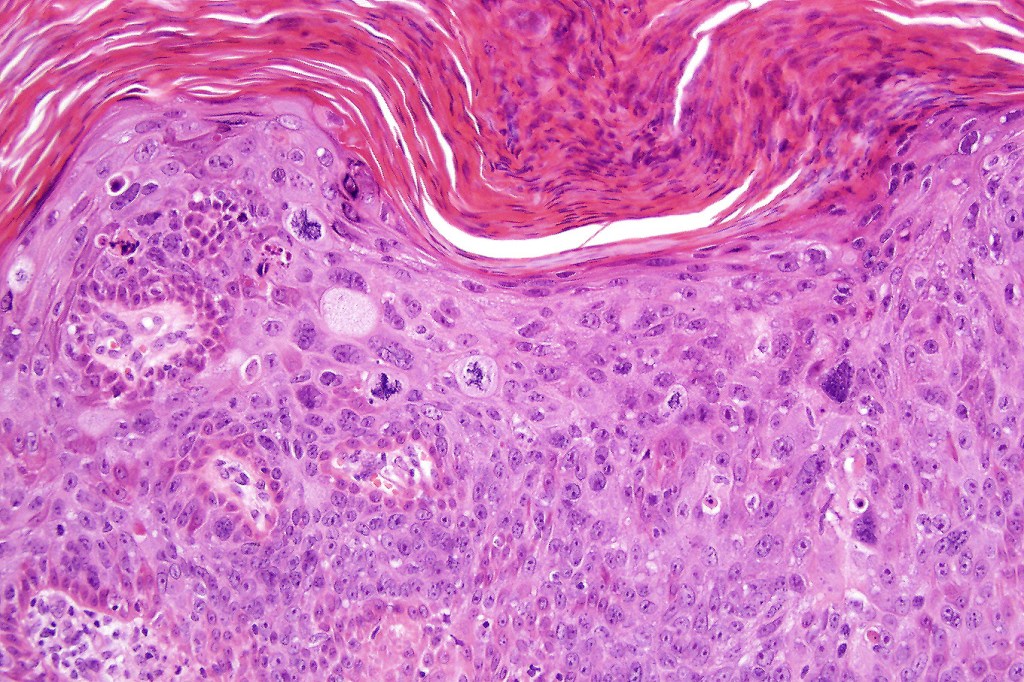

•Hyperkeratosis, parakeratosis & acanthosis

•Full thickness dysplasia (carcinoma in situ) involving the epidermis and intraepidermal adnexal elements

•Loss of maturation, nuclear pleomorphism, marked mitotic activity +/- abnormal forms

•Dyskeratosis & apoptosis

•Acantholytic variant